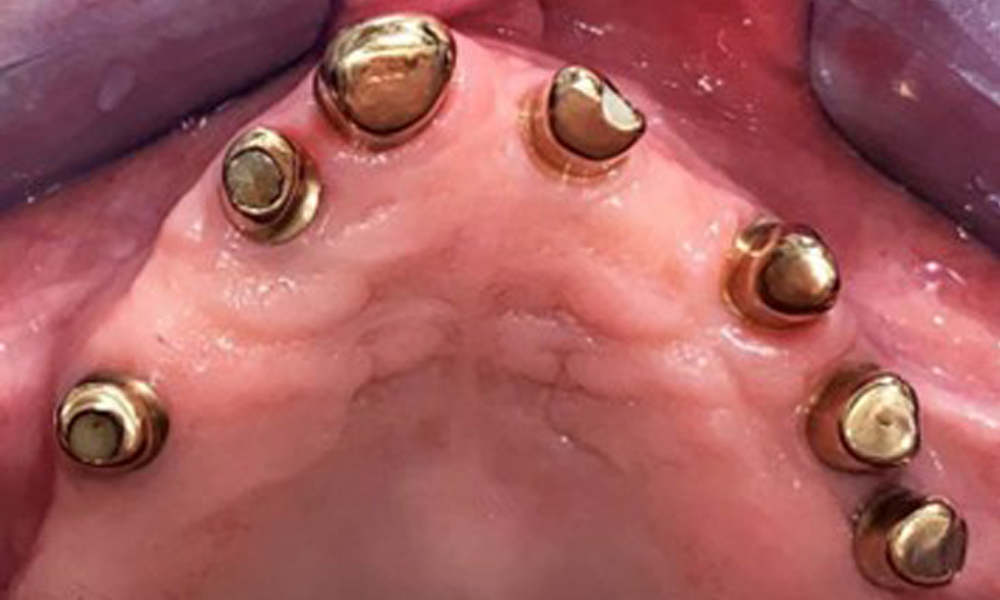

Occlusal view: Maxilla with tooth and implant-supported telescopic prostheses.

Fig. 2: Occlusal view: Maxilla with tooth and implant-supported telescopic prostheses

The dental findings are as follows: Combined removable implant and tooth-supported telescopic prostheses on implants 15, 13, 21, 23, 24, 25 and tooth 11 (Fig. 1, Fig. 2, Fig. 3). The patient was fitted with a fixed mandibular denture. Adequate bridges were present over 37 to 34 and 45 to 47 (Fig. 4), the crown margins were intact and there were no active caries. A composite filling with a marginal gap was present on tooth 43. There was mandibular gingival recession, exposing 1 to 3 mm of root surface. This also applies to 11.

The patient was fitted with a combined removable maxillary telescopic prosthesis more than 25 years ago (Fig. 1, Fig. 2, Fig. 3) and is very happy with her dentures. The patient has an adequate fixed denture for the mandible (Fig. 4).

Occlusal view: Maxilla with removable, palateless denture.

Fig. 3: Occlusal view: Maxilla with removable, palateless denture.